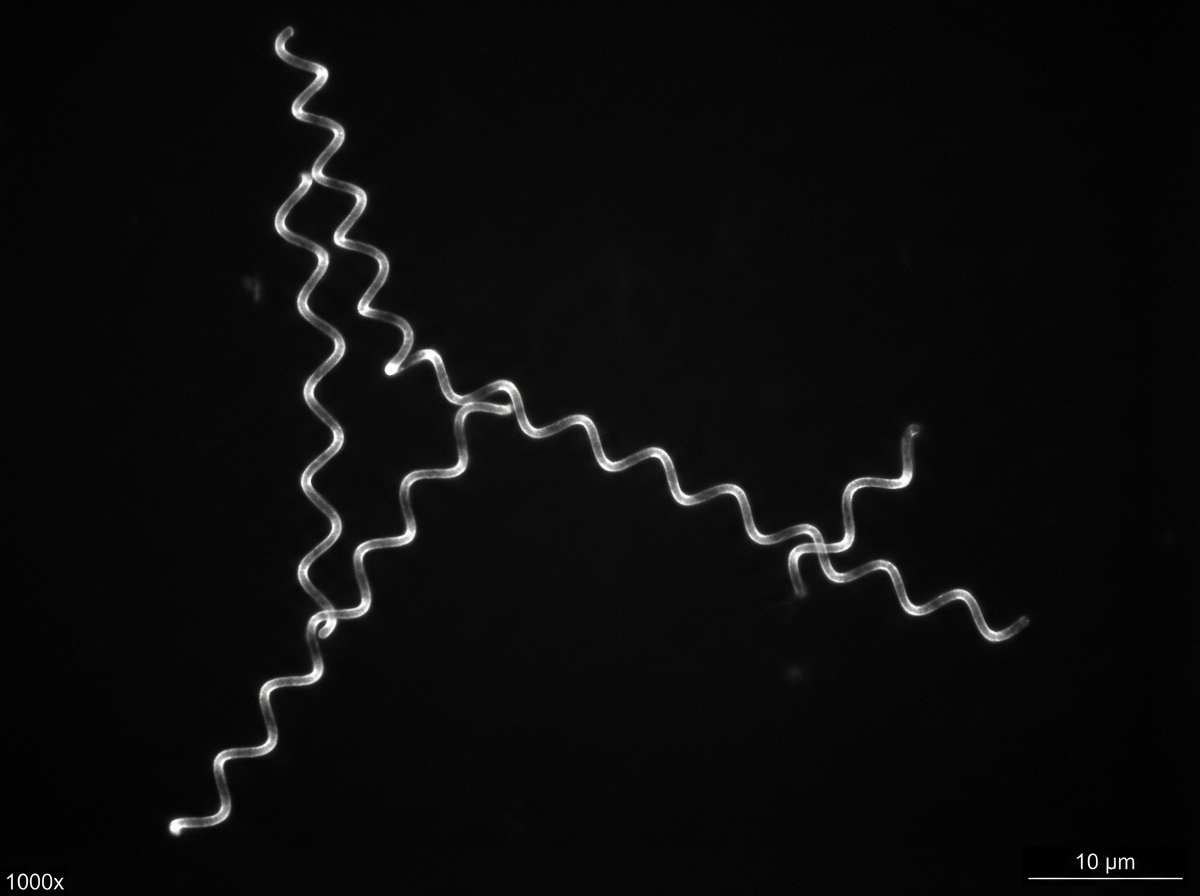

The diagnostic technique shown in the color plate is used for the diagnosis of which disease?

Explanation: ***Syphilis*** - **Dark field microscopy** is the gold standard direct diagnostic technique for syphilis, allowing visualization of **Treponema pallidum** with its characteristic **corkscrew morphology**. - This technique is particularly useful for examining **primary chancres** and **secondary lesions** where spirochetes are abundant and motile. *Typhoid* - Diagnosis relies on **blood culture**, **Widal test**, or **stool culture** for **Salmonella typhi**, not dark field microscopy. - **Rose spots** on the trunk are characteristic clinical findings, but microscopic diagnosis uses standard bacterial culture methods. *Cholera* - Diagnosed through **stool culture** on **TCBS agar** or **rapid diagnostic tests** for **Vibrio cholerae**. - **Rice water stools** are pathognomonic, and microscopy shows **comma-shaped bacteria** under standard light microscopy, not dark field. *Tetanus* - Diagnosis is primarily **clinical** based on **muscle spasms** and **trismus** following wound contamination. - **Clostridium tetani** is rarely isolated from clinical specimens, and diagnosis doesn't involve dark field microscopy.